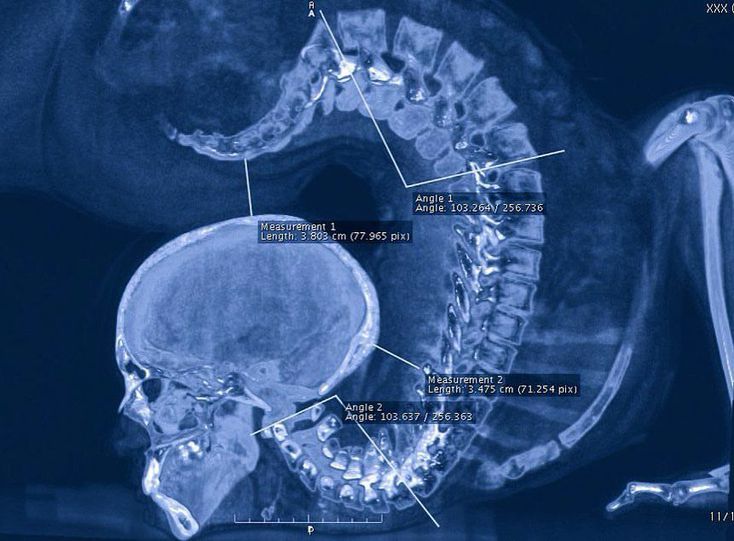

X-ray of a contortionist performing an exercise!! What you’re looking at is an x-ray of an individual in an extreme pose of spinal extension! Contortionists excel at extreme physical flexibility. They twists and bends their body into strange and unnatural positions. Note how the thoracic spine stayed almost completely straight. Contortionists, gymnasts, dancers, yogis, all of these athletes excel at their sport with exceptional spinal flexibility. But at what cost? The spine forms the central axis of the skeleton, supports the skull, and gives attachment to the thoracic cage, pectoral girdle, and upper limb. It combines strength with great flexibility as it has many joints close together. Movements of the spine are possible due to intervertebral discs, and with the fulcrum of movement occurring primarily around the nucleus pulposus. Specialized motion occurs at the atlanto-occipital and atlantoaxial joints, which do not contain a disc. Flexion and extension are common to all parts of the spine; a significant degree of flexion/extension can be achieved at the atlanto-occipital joint, cervical and lumbar spine, but is restricted in the thoracic spine. Lateral flexion is free at the atlanto-occipital joint, cervical and lumbar spine, but less free in the thoracic spine. Rotation is greatest at the specialized atlantoaxial articulations, and to a lesser degree in the cervical and lumbar spine. A medical publication from 2008 suggests that long-term damage to the spine is common in long-term contortion practitioners. A study of five practitioners using magnetic resonance imaging (MRI) by Peoples et al. documented limbus vertebrae, intervertebral disc bulges, and disc degeneration. Three of the five practitioners also reported back pain.